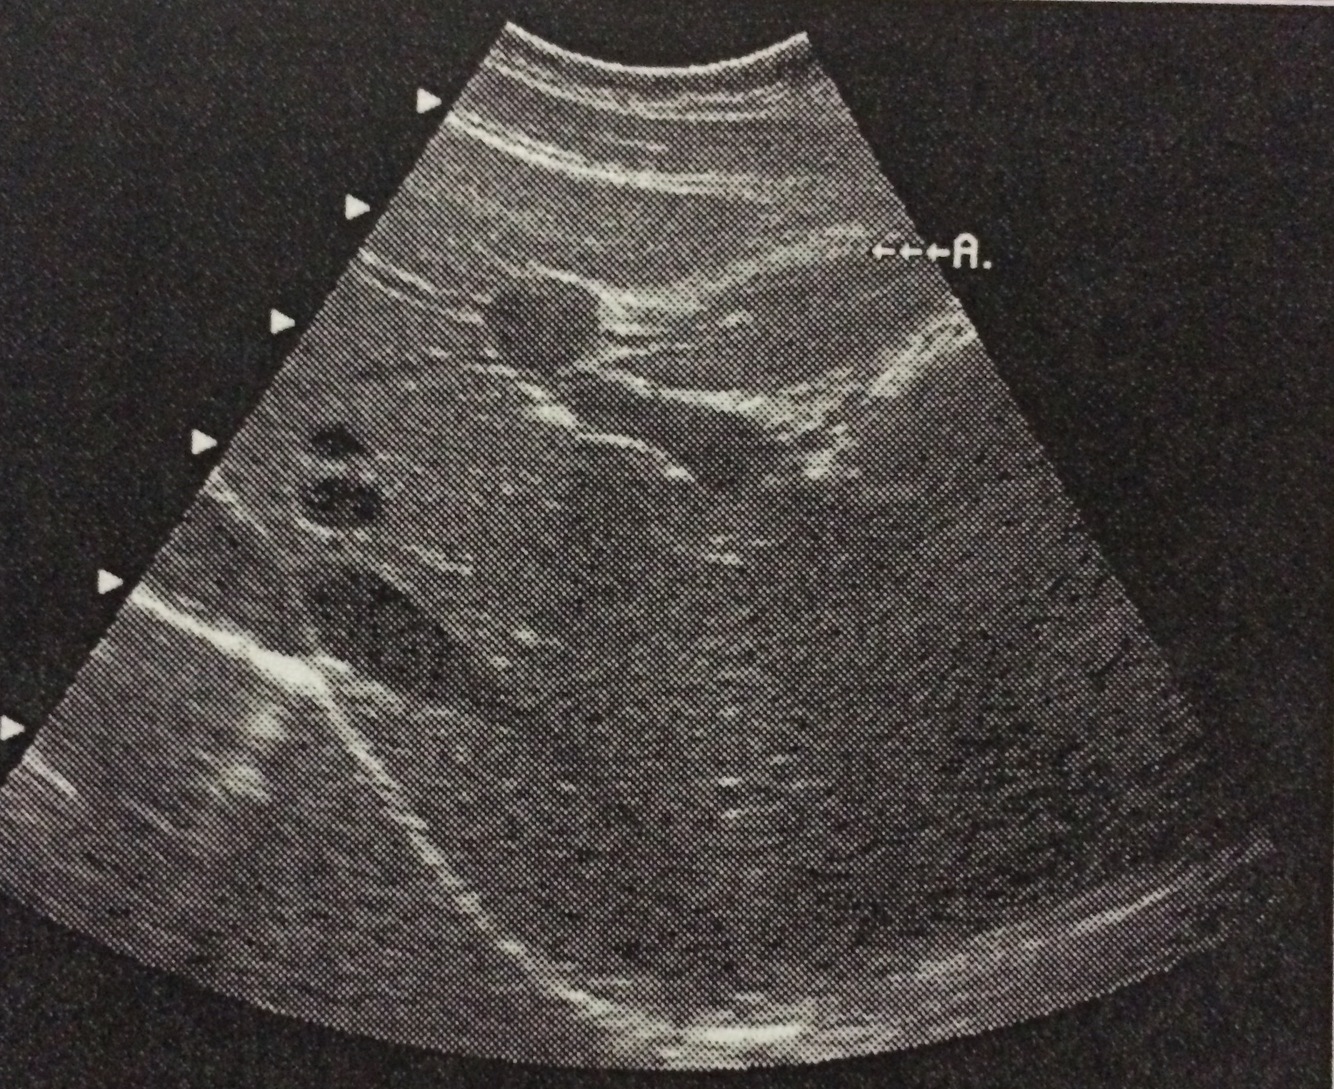

Identify the structure labeled A in this image of the liver.

Ligamentum teres